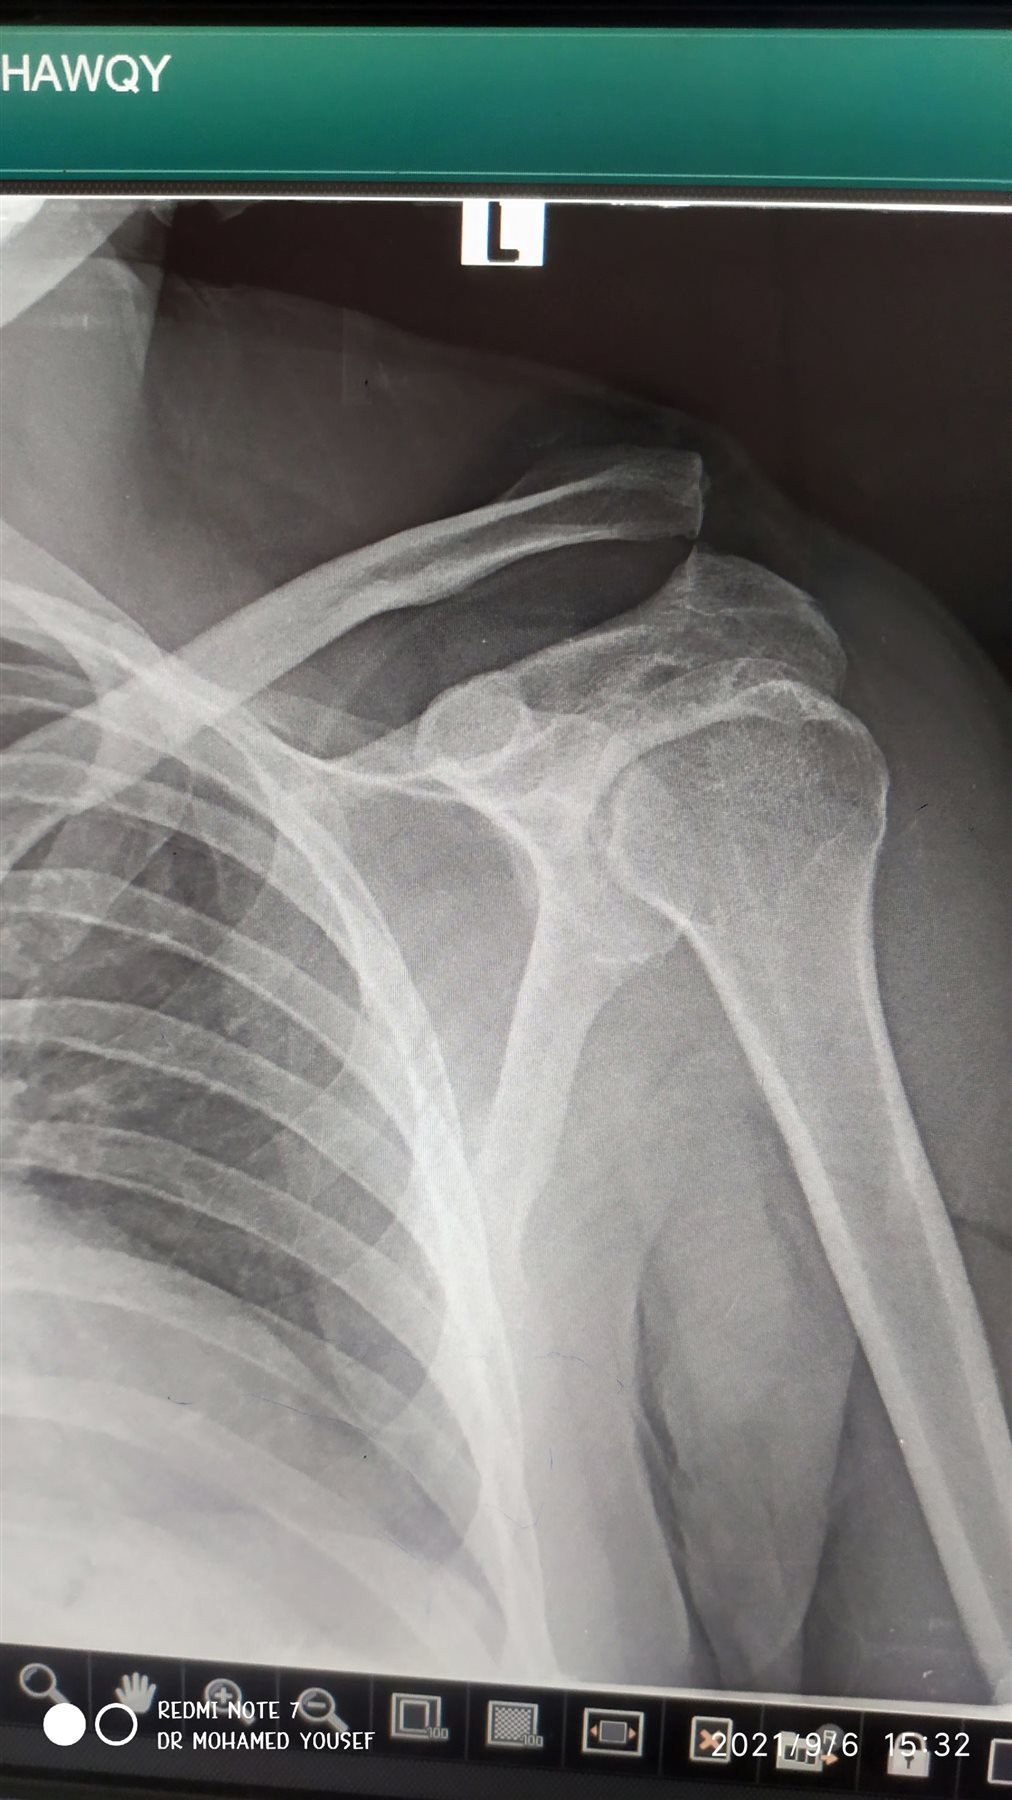

ووفقا لما جاء فى موقع “ دوتش فيله” فإن من أهم أسباب آلام الكتف التعرض لحادث أو الاصطدام بجسم صلب مما يؤدي لخلع مفصل الكتف، وهو ما يجعل تحريك الكتف عملية شبه مستحيلة بسبب الألم الشديد.

وتتسبب الترسبات الجيرية في أنسجة الكتف، للإصابة بما يعرف بتكلس الكتف والذي ينتج عادة عن ضعف ضخ الدم في تلك المنطقة، وهناك بعض الأعراض المرتبطة بهذه المشكلة وأهمها صعوبة في رفع الذراع لأعلى، ونادرا ما تظهر الأعراض التي تكشف الإصابة بالالتهابات مثل الانتفاخ والشعور بارتفاع حرارة المنطقة المصابة.